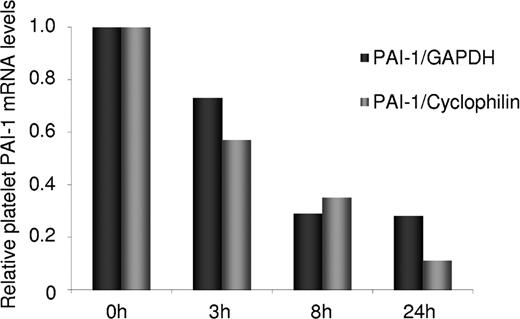

The degradation rate of PAI-1 mRNA compared to GAPDH and cyclophilin was analyzed by incubation of platelets for 0, 3, 8, and 24 hours followed by mRNA extraction and analysis of mRNA levels for the 3 genes by real-time PCR. As shown in Figure 2, the degradation rate of PAI-1 mRNA was found to be 4-fold higher than that of GAPDH and 8-fold higher than that of cyclophilin.

The relative degradation rate of platelet PAI-1 mRNA in comparison to the 2 endogenous reference genes, GAPDH and cyclophilin. mRNA extracted from platelets incubated 0, 3, 8, and 24 hours was determined by real-time PCR. The degradation rate of PAI-1 mRNA was 4-fold higher than that of GAPDH and 8-fold higher than that of cyclophilin.

The relative degradation rate of platelet PAI-1 mRNA in comparison to the 2 endogenous reference genes, GAPDH and cyclophilin. mRNA extracted from platelets incubated 0, 3, 8, and 24 hours was determined by real-time PCR. The degradation rate of PAI-1 mRNA was 4-fold higher than that of GAPDH and 8-fold higher than that of cyclophilin.